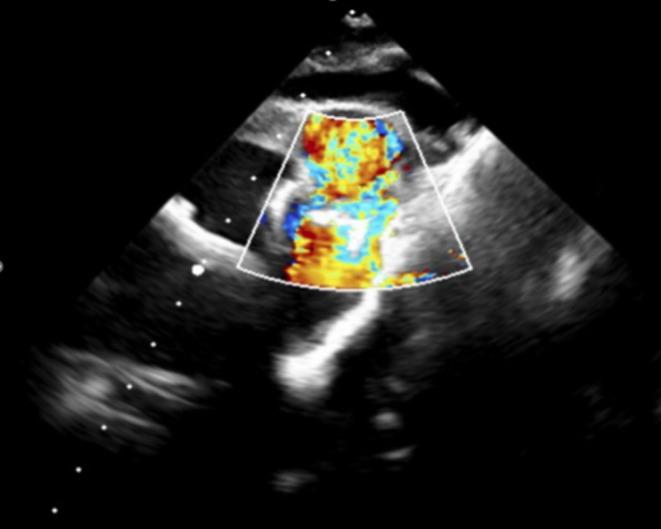

Spontaneous Resolution of Hemolysis After Ventricular Septal Defect Closure With an Amplatzer Device.

A wait and see approach can be maintained in cases with mechanical hemolysis after percutaneous VSD closure, even when the cause is not homogeneous.

对于经皮室间隔缺损封堵术后发生机械性溶血的病例,即使病因并不相同,也可采取观察等待的方法。